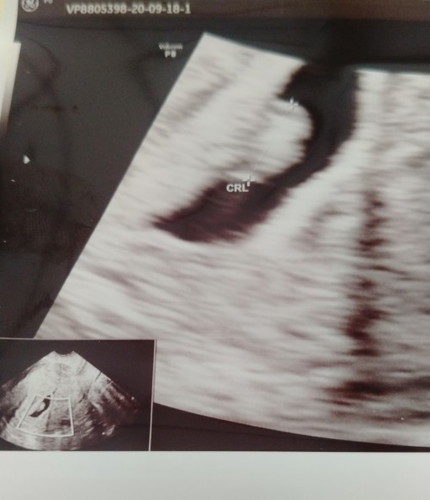

hai dan salam semua kpd smua .. Saya mahu tanya ... hari tu ada spotting coklat kluar sikit2 , masa tu 5 week . doktor beri ubat penguat rahim. spotting tu kadang2 je ada kluar , itu pun sikit saja pada pmukaan panty sahaja . smpai skrang dh 7 week pun msih mcm tu . scan 7 week hr tu dh ada nmpak degupan jantung . doktor cakap gmbr scan nampak ada kempis tidak cantik mbulat , dia ckap susah mau katakan samada abortion atau tidak , jd dia bagi lagi appointmnt 2 week akan datang. jd skarang saya risau sbb ni anak ptama fan umur saya pun dah capai 37 , mmg mharap sangat baby tu kekal dsitu . ada sesiapa yg pernah alami perkara yg sama dgn saya kah ? adakah baby tu dpt mbesar melekat dgn selamat ? kpd yg lebih arif lagi , agak2 nya brp persen kah baby tu dpt btahan dan kmungkinannya bjaya ? normal ke tidak mcm tu ? ada juga kawan2 cadangkan injection dekat private lbih bkesan . tp doktor hr tu ckap inj tu sama dgn pil pnguat rahim yg saya makan sekarang . jd ....kawan2 beriya2 suggest tuk pegi inj , lagi bagus diaorg cakap . patutkah saya dptkan inj tu? #firstbaby #seriusnanya #firstbaby #bantusharing